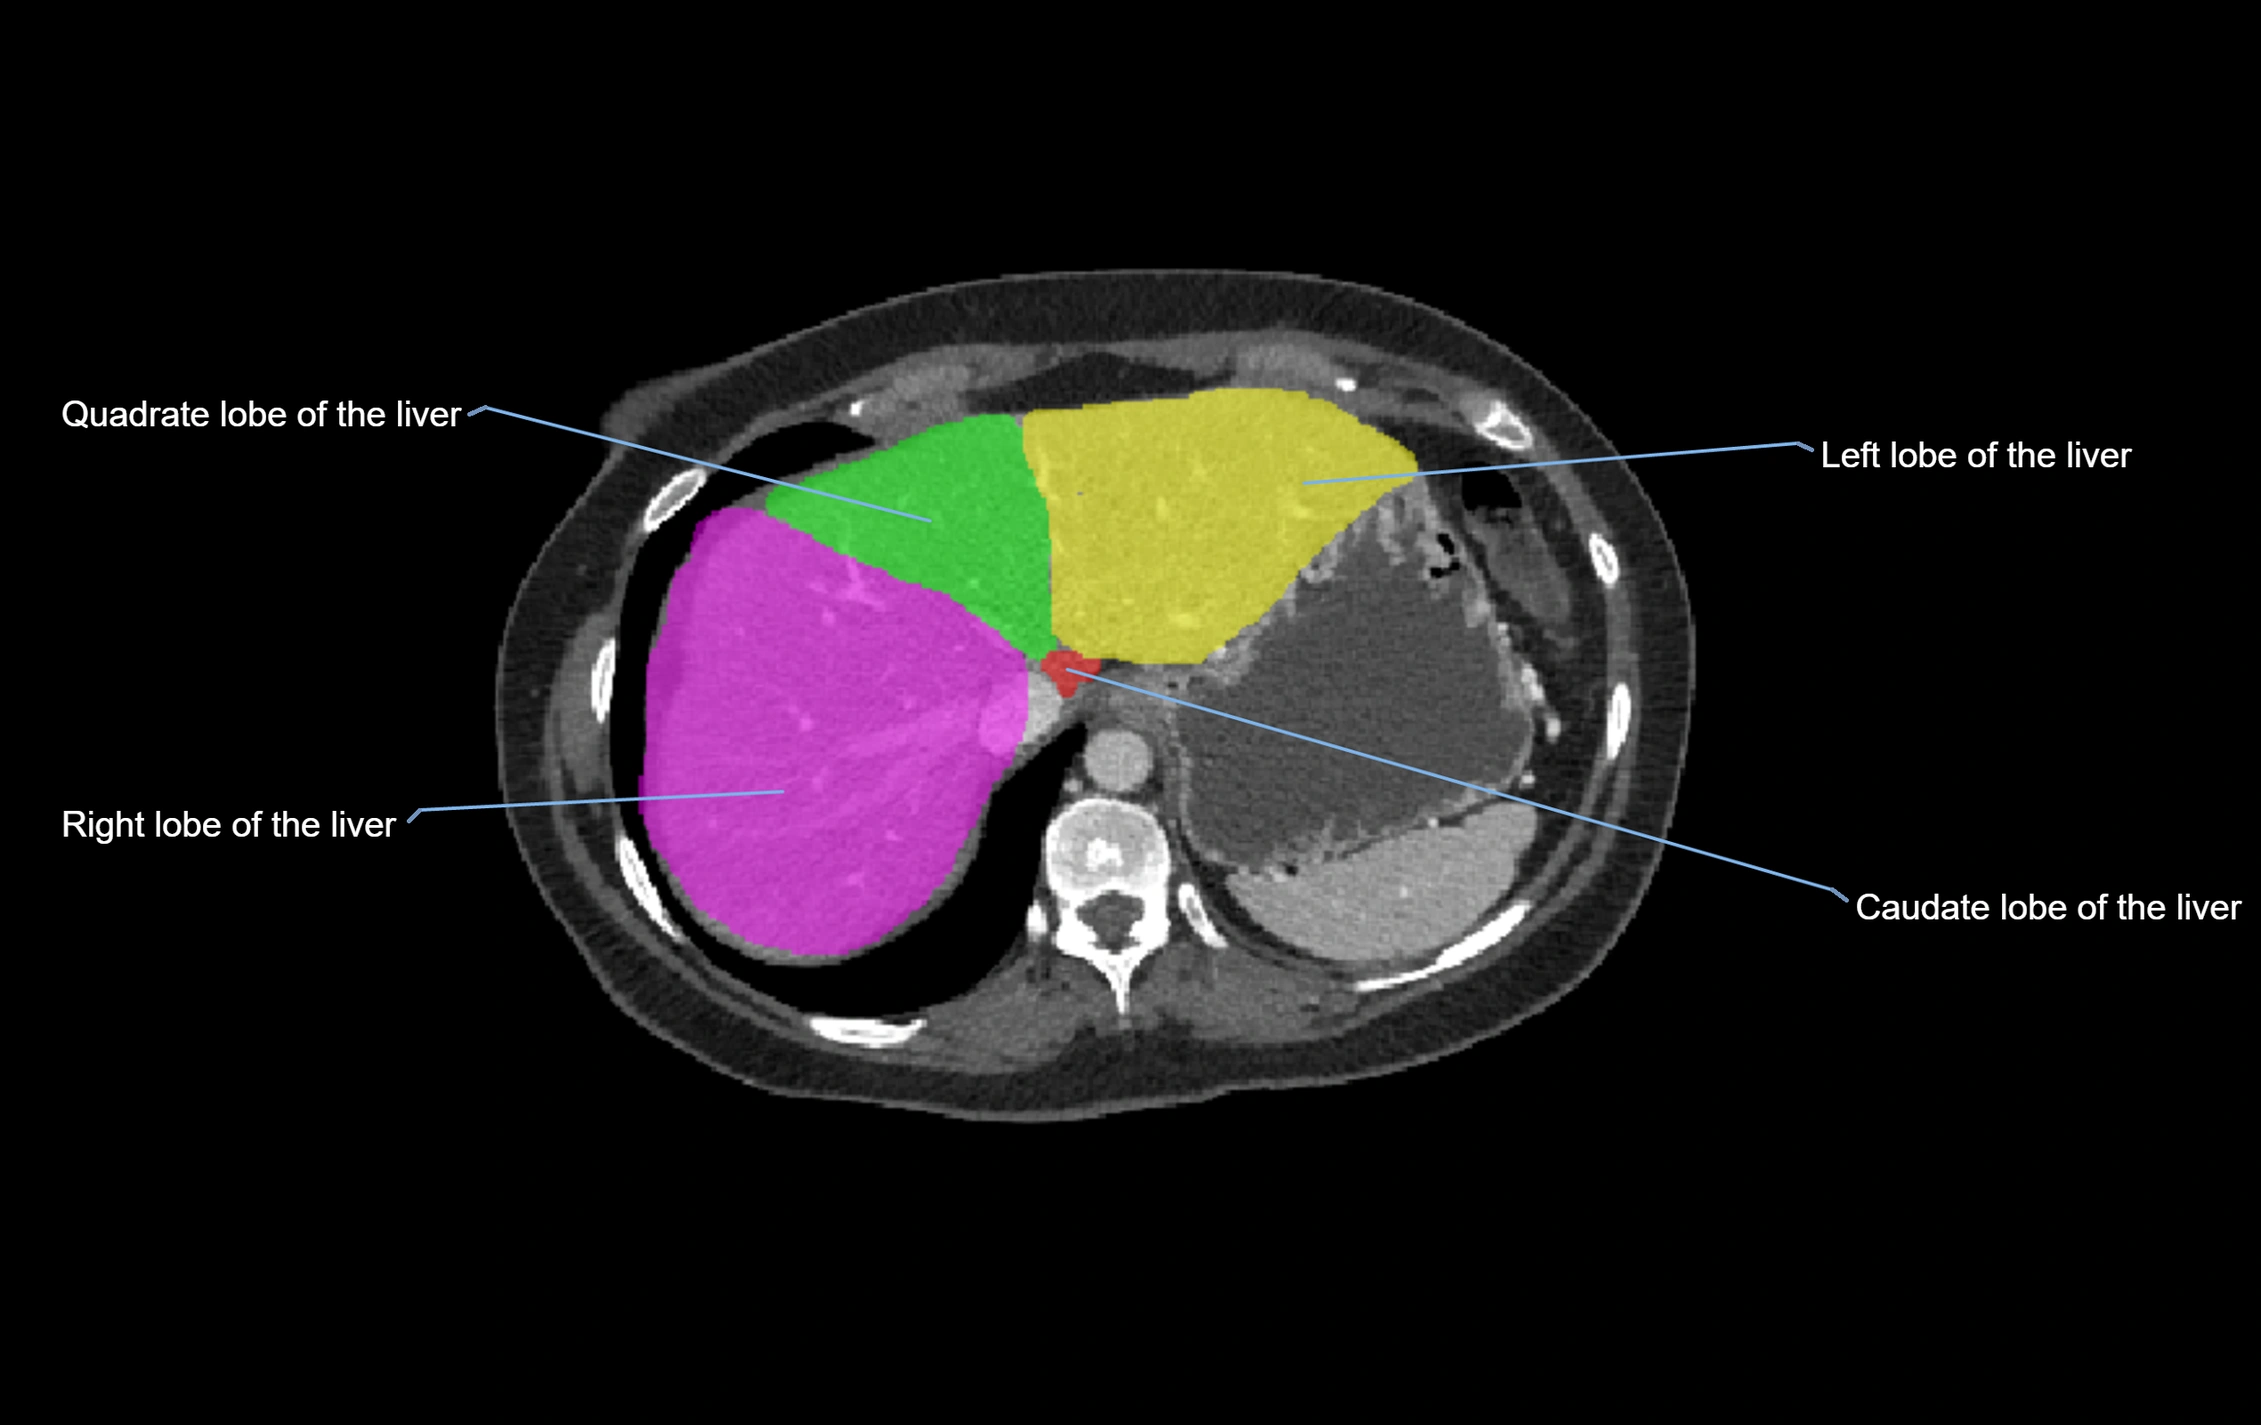

CT Image

image